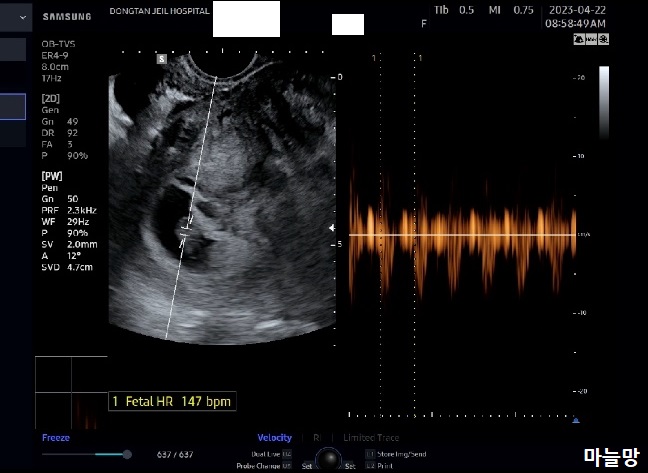

초음파를 보는데, 최초로 생긴 큰 아이는 점점 더 자라서 이젠 제법 크기가 커진 상태였어요. 처음으로 커다란 심장소리를 듣기도 했고요.

그리고 초음파를 돌려 나중에 생겼던 아기집을 비췄는데, 아기집속이 텅텅 비어 있었습니다.

저번주에 처음으로 발견되어 심장소리까지 들었지만 약했나 봐요.